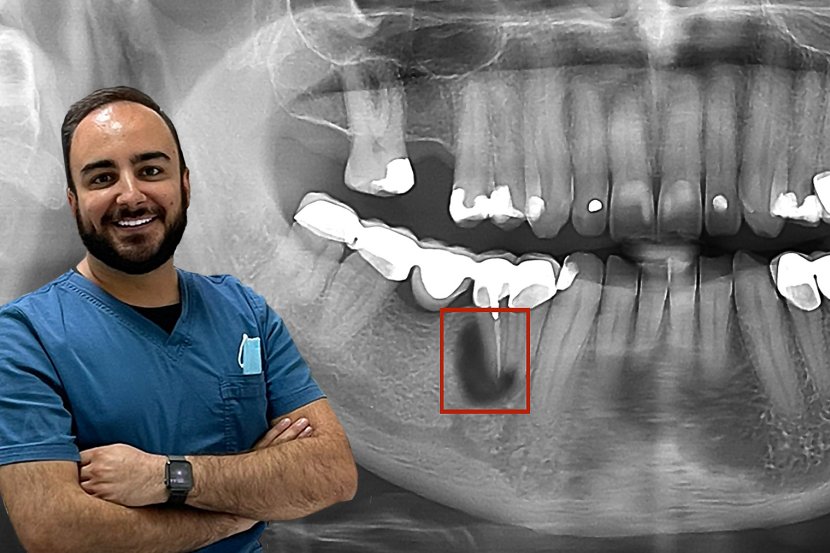

Gangrena, nastavak Proces nastanka gangrene zuba Foto: en.webdento.com

Gangrena zuba, lečenje Proces lečenja gangrene zuba Foto: en.webdento.com